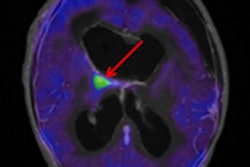

Whole-body FDG-PET/MRI exam of a 1-year-old girl with metastatic teratoma. Combined PET/MRI enables simultaneous acquisition of whole-body MRI (A) and PET (B) as well as local MRI (C.I). MRI shows a paravertebral metastasis (C.I, red arrow), which is metabolically active on FDG-PET (C.II, PET/MRI fusion image).

Whole-body FDG-PET/MRI exam of a 1-year-old girl with metastatic teratoma. Combined PET/MRI enables simultaneous acquisition of whole-body MRI (A) and PET (B) as well as local MRI (C.I). MRI shows a paravertebral metastasis (C.I, red arrow), which is metabolically active on FDG-PET (C.II, PET/MRI fusion image).The PET/CT results suggested an additional MRI scan for local staging and therapy planning for four patients, but the recommendation proved unnecessary except in one case.

"This additional examination [based on PET/CT] became unnecessary after PET/MRI, where local imaging was performed together with whole-body staging in one single examination," the authors wrote. "In one patient, the detection of a suspicious morphological MR correlate for focal tracer accumulation initiated close follow-up imaging and extended treatment."